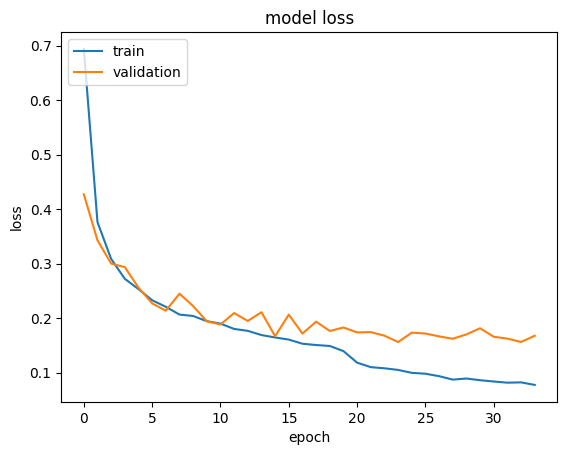

The dataset has been trained using our custom-made model dividing the whole data set into a batch size of 64 and later a portion of the dataset that has been extracted before the training as the test dataset and has been used in order to measure the performance of the model using various performance metrics. In addition to our custom model, the performance of the pre-trained model VGG-19 on the same dataset has been determined to get a clear comparative idea between the custom model and the pre-trained model. Accuracy of the overall dataset and precision, F-1 Score and sensitivity of each of the classes for each of the models has been calculated as the measurement of performance evaluation and has been depicted in Table V.

Firstly, if we focus on the models, the self-developed custom model has a clear superiority in terms of performance in all the performance metric. VGG-19 achieves an accuracy of 92.77% on the overall dataset, whereas the custom model reaches 94.87% exceeding that of VGG-19. Not only accuracy but also in terms of other metrics, the custom model always gains a higher value than the VGG-19 model in any of the classes. The precision, F-1 Score, sensitivity values of 0.921, 0.928 and 0.921 respectively of the CNV class from the custom model compared to the 0.898, 0.917 and 0.898 values from VGG-19 model can be given as an example that infers the previous statement. Fig 5 illustrates the confusion matrix of all the labels which is produced from the result of the proposed model

Secondly, another important observation from Table V is among the four classes CNV and Normal class has been comparatively superior in case of all the metrics, as the precision, F1-score and recall of CNV from the custom model are 0.967, 0.966 and 0.967 respectively and that values for the Normal cases are 0.977, 0.964 and 0.977 and similar scenario for the pre-trained model. The reason behind their better performance is the presence of their larger number of data and as the larger, the number of the data, the better the performance of any CNN model would be. The latter statement is also proven by the fact that the Drusen class has provided the poorest result and the quantity of data for this class is also the smallest So, in the end, it can be inferred that the performance of the self-developed custom model, as well as the pre-trained model, can easily be upgraded by collecting more data.

Overall, in terms of computation 6-layer custom model is more efficient than VGG-19. The parameters to be trained in our model is 423,460 wherein VGG-19 it is 21,011,740. Again, the model weight size of 6-layer custom model is less than 2 MB having a clear edge over the VGG-19.